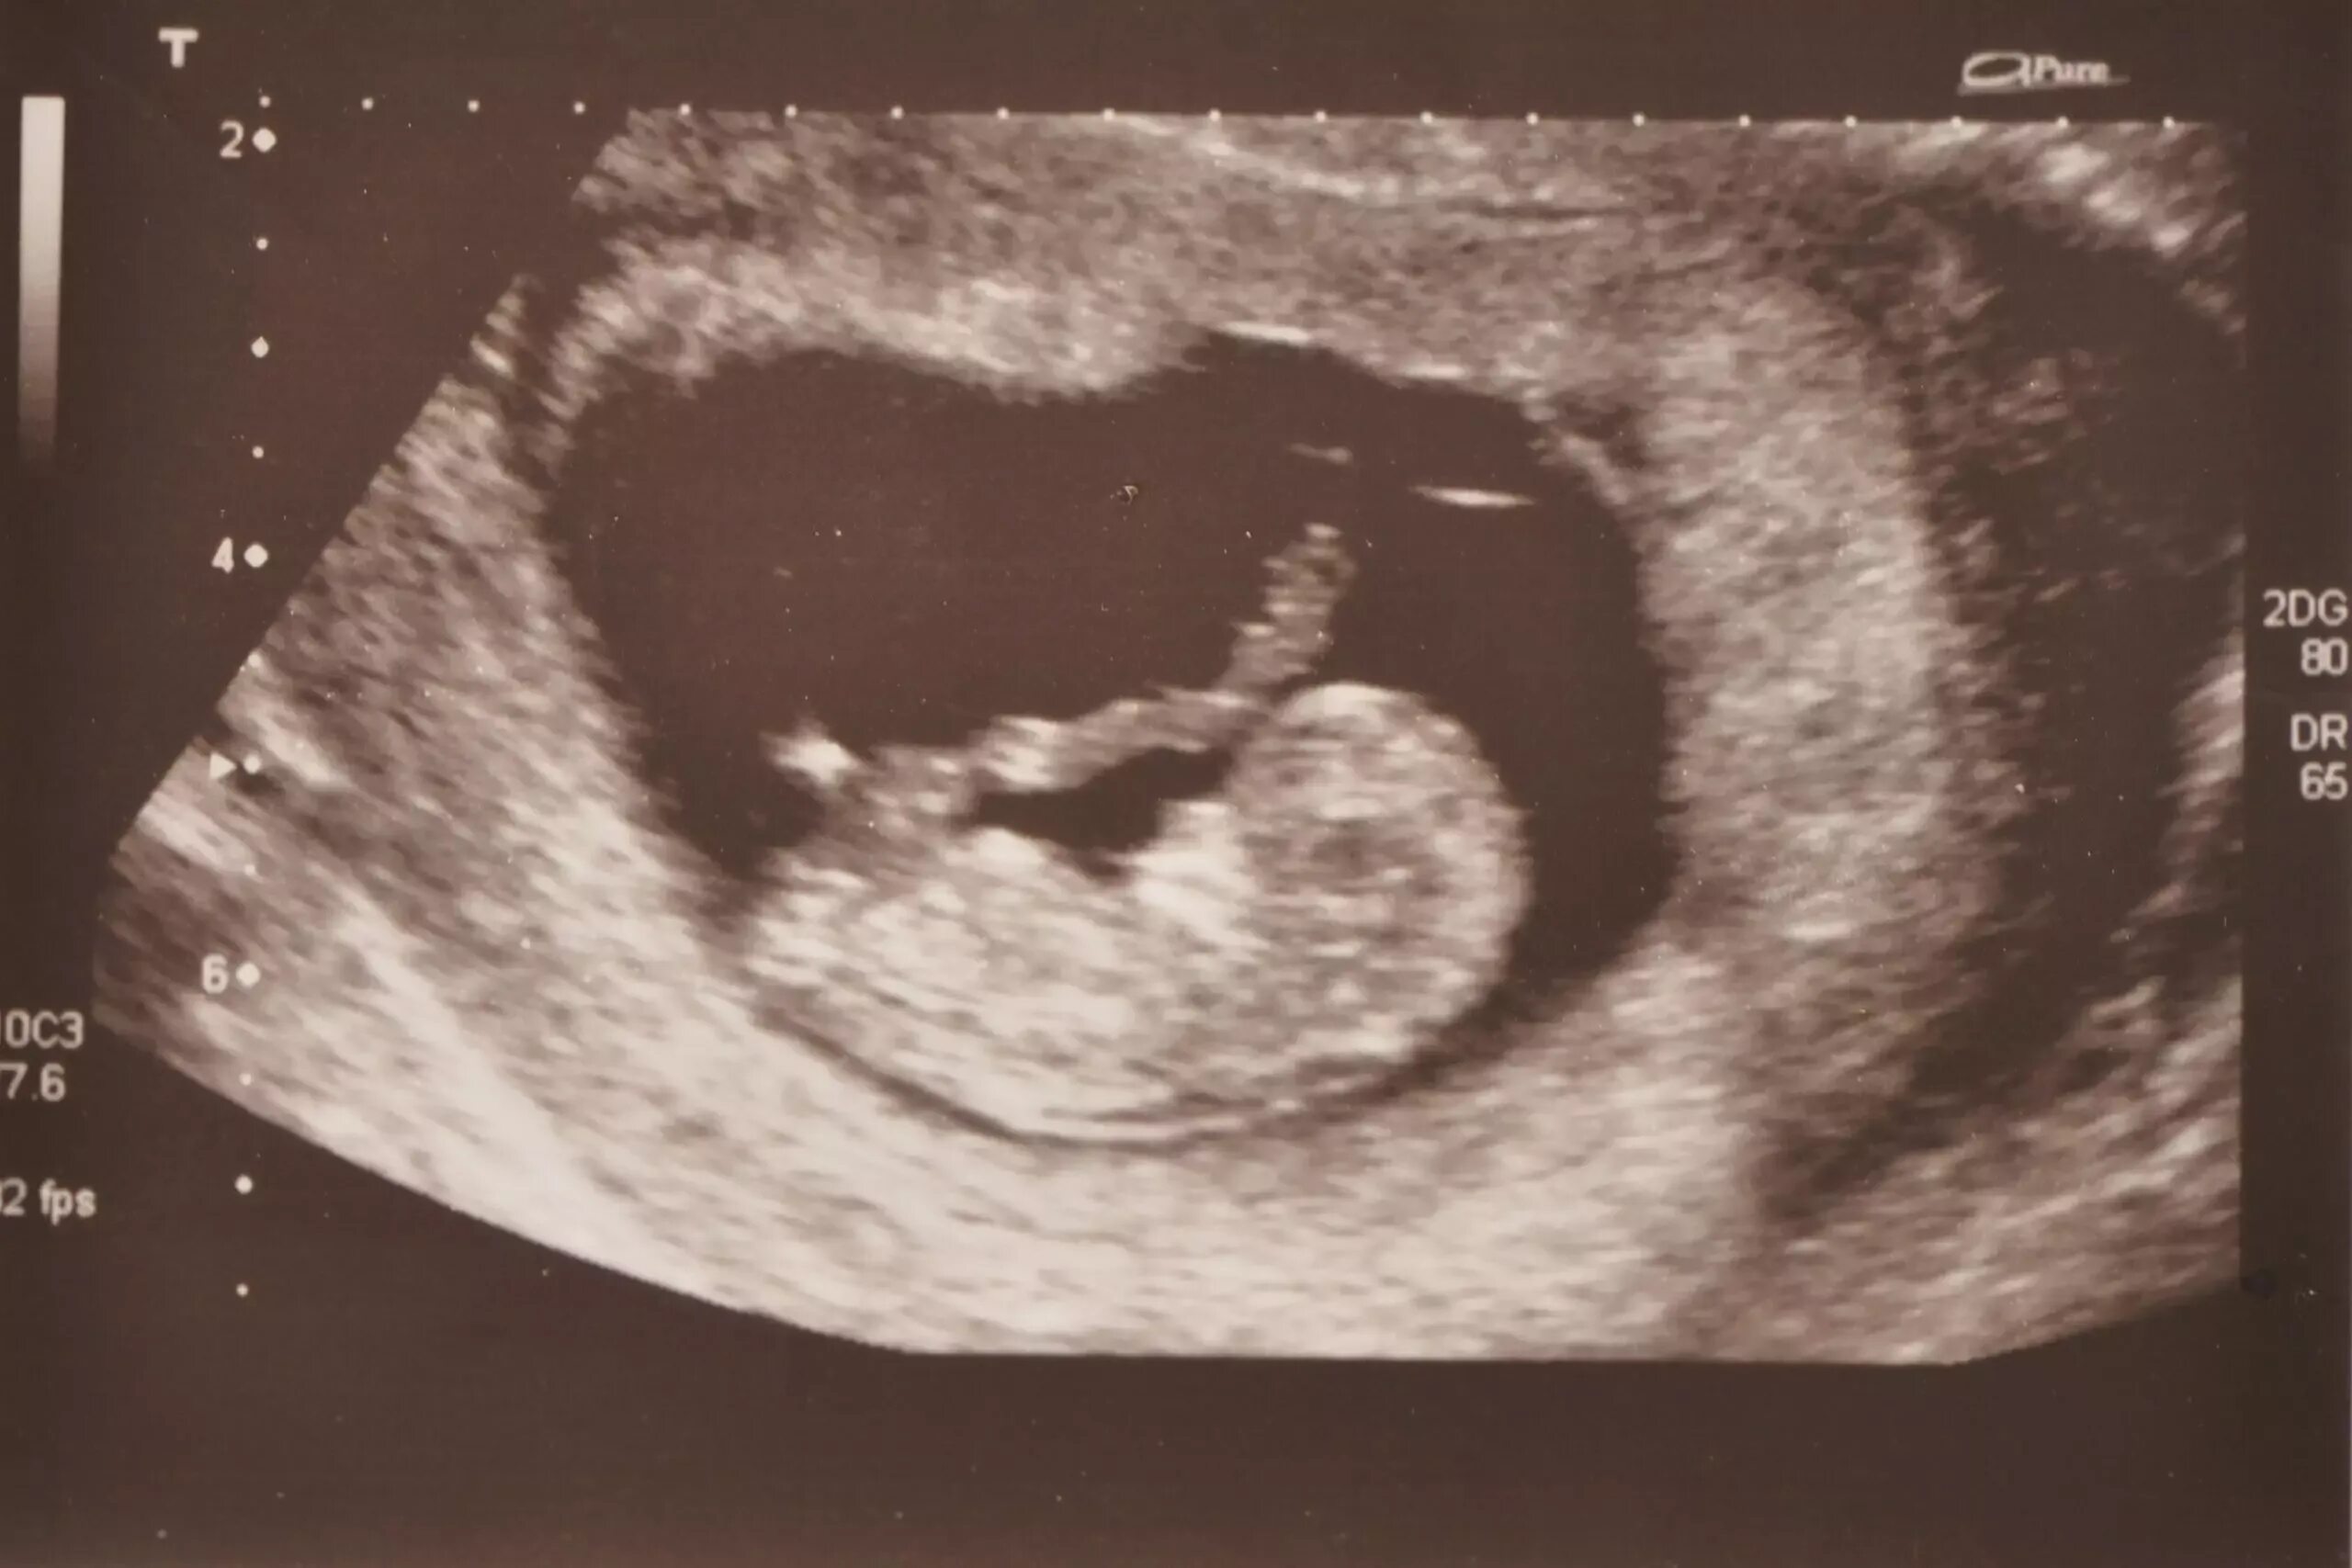

10 week old